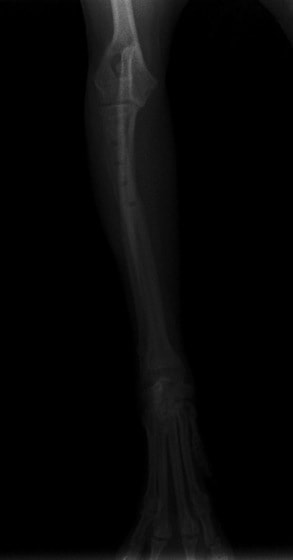

ペルシャ猫 11ヶ月齢 雄

他院にて左大腿骨遠位の成長板骨折(salter-harrisⅠ型)が認められており、治療相談を目的として来院。当院にて、キルシュナーワイヤーを用いたピンニングにより骨折部位の整復を行いました。術後の経過は良好で、現在も経過観察中です。

術前レントゲン

術後レントゲン